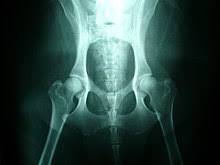

Osteosarcoma is less common in cats. With osteosarcoma cancer, which generally occurs in femurs. Bone cancer in dogs what you need to know about osteosarcoma (part 1) vlog 71. Osteosarcoma is an aggressive cancer that can develop in any bone of the body but the majority is seen in the limbs. Bone cancer in dogs is rather common, with osteosarcoma as the most common type of bone tumor.

The cartilage on the end of the bones is surgically removed, and a bone graft is. The median age at diagnosis is. Bone cancer in dogs is rather common, with osteosarcoma as the most common type of bone tumor. It can grow in any of the bones in the body. It tends to spread to the lungs very early in the course of the disease, and accounts for some 80 percent of the primary bone cancers found in dogs. Symptoms of bone cancer in dogs. Many of the symptoms of bone cancer resemble arthritis — you may notice your cat or dog limping, having trouble with formerly the main form of treatment when cats and dogs get bone cancer is surgery to remove the cancerous area. With osteosarcoma cancer, which generally occurs in femurs. Painkillers prescribed for what's thought to be arthritis can alleviate the problem in the short term, but it worsens the prognosis for bone cancer by delaying more appropriate treatment. A company based in houston (valco instruments) has developed a small drill that can deliver a very small amount of radioactive isotope to the tumor, thereby targeting the cancerous cells directly. Hemorrhagic effusion with ruptured hemangiosarcoma. Younger dogs, although this could be due to late diagnosis. Stomach cancer often is not diagnosed until the later stages.

This aggressively malignant bone cancer most often strikes large or giant breeds, typically in the long bones of the legs. Vitex agnuscastus extracts for female reproductive disorders: It can lead to crippling lameness and painful. Does bone cancer in dogs spread quickly? Stomach cancer often is not diagnosed until the later stages. This bone tumor affects flat bones such as those around the nose, skull, and ribs. Panosteitis, osteochondrosis, and hypertrophic osteodystrophy are the three most common metabolic bone disorders seen in dogs. Diet and exercise will be key in the maintenance of a good quality of life. Osteosarcoma is less common in cats. In fact, noncancerous bone tumors are much more common than cancerous ones. Our dogs have bones that are connected together with soft tissue (muscle arthritis in dogs: Risk of infections in rheumatoid arthritis patients treated with tocilizumab. Elderly people with conditions such as arthritis are especially vulnerable.